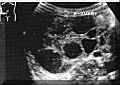

Theca-lutein

cysts

are

the

ovarian

response

to

excess

human

chorionic

gonadotropin

(hCG)

secretion

by

GTNs.

These

formed

large

follicles

that

full

of

liquid

and

have

smooth

walls,

partially

or

totally

occupy

ovaries

(Picture2).

Picture2.

cysts.